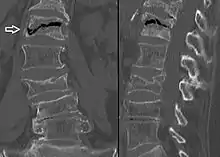

In the early stages, bone scintigraphy and MRI are the preferred diagnostic tools.[11]

X-ray images of avascular necrosis in the early stages usually appear normal. In later stages it appears relatively more radio-opaque due to the nearby living bone becoming resorbed secondary to reactive hyperemia.[2] The necrotic bone itself does not show increased radiographic opacity, as dead bone cannot undergo bone resorption which is carried out by living osteoclasts.[2]